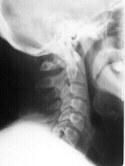

Few if any headache sufferers have a normal neck.  Many have excessive muscular tension alone but the vast majority have a loss of normal spine posture.  In the spine the neck has a natural forward curve of about 40 degrees.  This insures proper balance of the head on the torso.  But through injury, poor posture or birth defect the forward curve can become lost.  This loss can even result from forceps delivery or birth trauma.  Loss of the forward curve mean excess strain to the neck muscles and meninges and a lifetime of headaches can result.  Obviously no medication will change posture or mechanical irritation of the neck.

Normal Curve